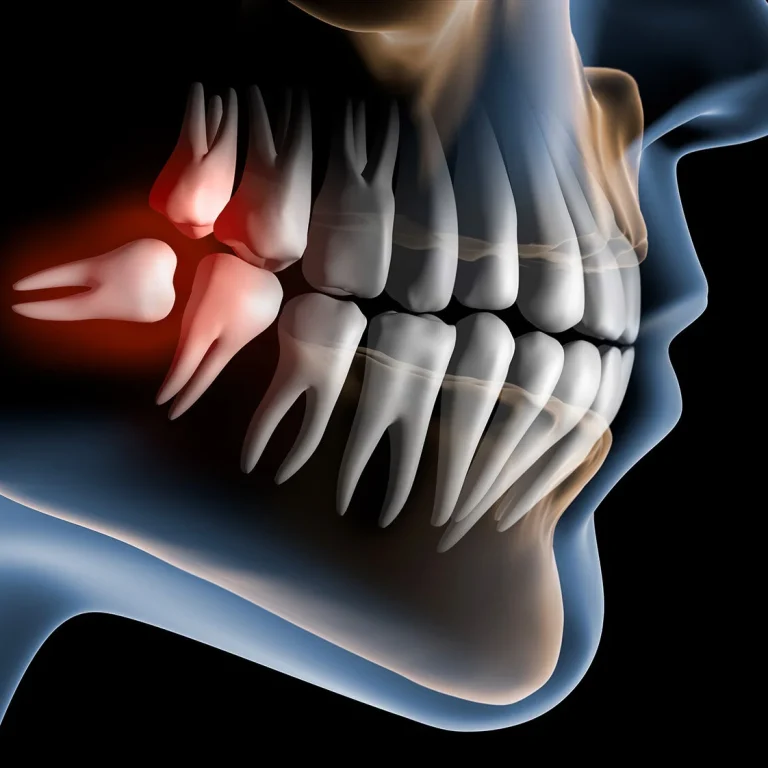

What Happens During Wisdom Tooth Removal - Step by Step For many patients, the idea of having wisdom …

Why Do Wisdom Teeth Cause So Many Problems? Almost everyone knows someone who’s had their wisdom teeth removed, …